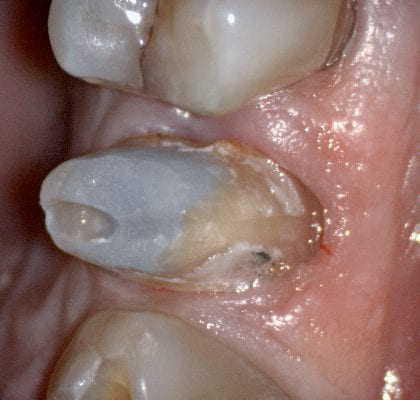

Immediate Post Op

The remaining decay and previous build up material was removed just prior to bonding the restoration with NX3 dual cure resin cement so the dentin was exposed for the least amount of time possible.